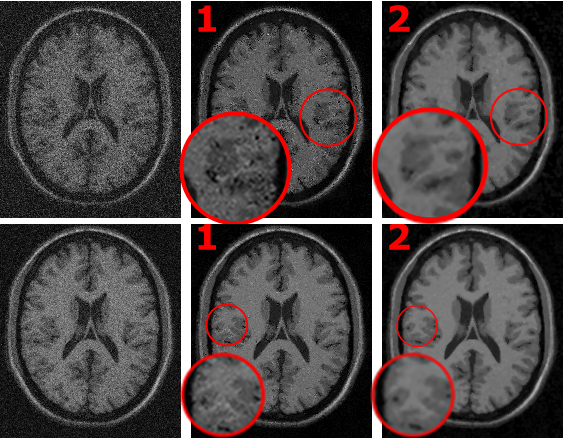

It can reach an acceleration factor of 20x over the original implementation, with an improved performance for medium-low SNR images (in the figure, (1) is the original Non-local Means and (2) is generated with this software).